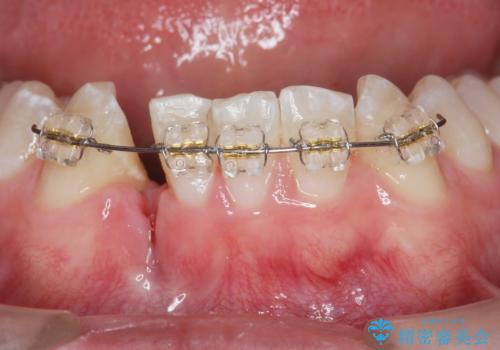

- 前歯の違和感、痛みの改善を希望され来院されました。

X線写真および歯周組織検査より、歯の破折 周囲骨の高度な吸収が認められました。

抜歯後、インプラントによる審美・機能改善を希望されたのでインプラント埋入に先立ち吸収した骨の再生を計画します。